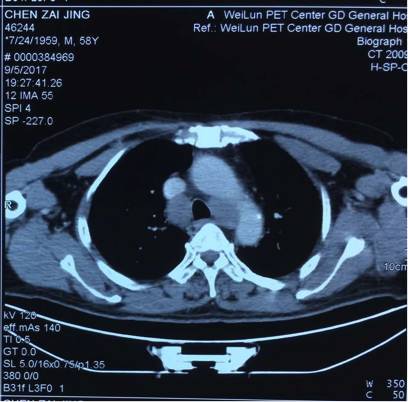

5. 2017-9-5广东省人民医院PET提示:右肺下叶肿物2.8*2.7cm,SUV 22.3,双侧颈部、双侧气管旁、隆突下、食管旁、右侧肺门淋巴结肿大,代谢升高,考虑为转移灶,右侧肾上腺转移灶,具体结果见下图:

(准备行经皮肺穿刺活检时图像)